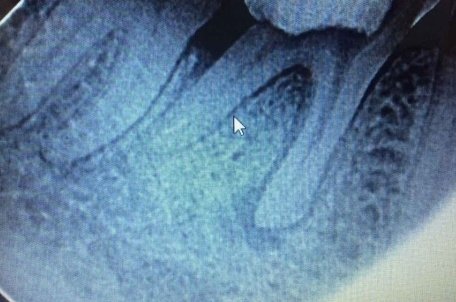

У меня зуб болит. Я его лечила 3 года назад. Мне поставили штифт в декабре 2015, он опять заболел, сделали снимок, оказалось, что он был плохо пролечен. Сняли пломбу, смогли пройти только один канал, во втором канале материал, третий мне врач не смог пройти (инструмент упирался в десну). Тогда еще врач сказал, что этот зуб только удалять, я не согласилась на удаление и мне его просто перекрыли пломбой, теперь опять побаливает.

В зубе имеется перфорация, к сожалению, такой зуб спасти и сохранить невозможно.